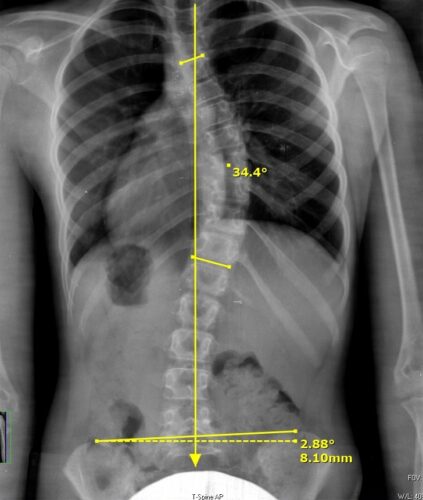

اعوجاج العمود الفقري هو انحناء غير طبيعي يحدث في الجانب، أي يمينًا أو يسارًا، وغالبًا ما يصاحبه دوران في الفقرات. لذلك، لا يكون مجرد انحناء بسيط، بل حالة ثلاثية الأبعاد تؤثر على شكل الجسم بالكامل.

غالبًا ما يظهر اعوجاج العمود الفقري خلال فترة المراهقة، خاصة مع النمو السريع بين عمر 10 إلى 16 سنة. ومع ذلك، يمكن أن يظهر في أي عمر، سواء عند الأطفال أو البالغين.

اعوجاج العمود الفقري أكثر تعقيدًا لأنه ثلاثي الأبعاد، بينما تقوس الظهر يكون في اتجاه واحد.